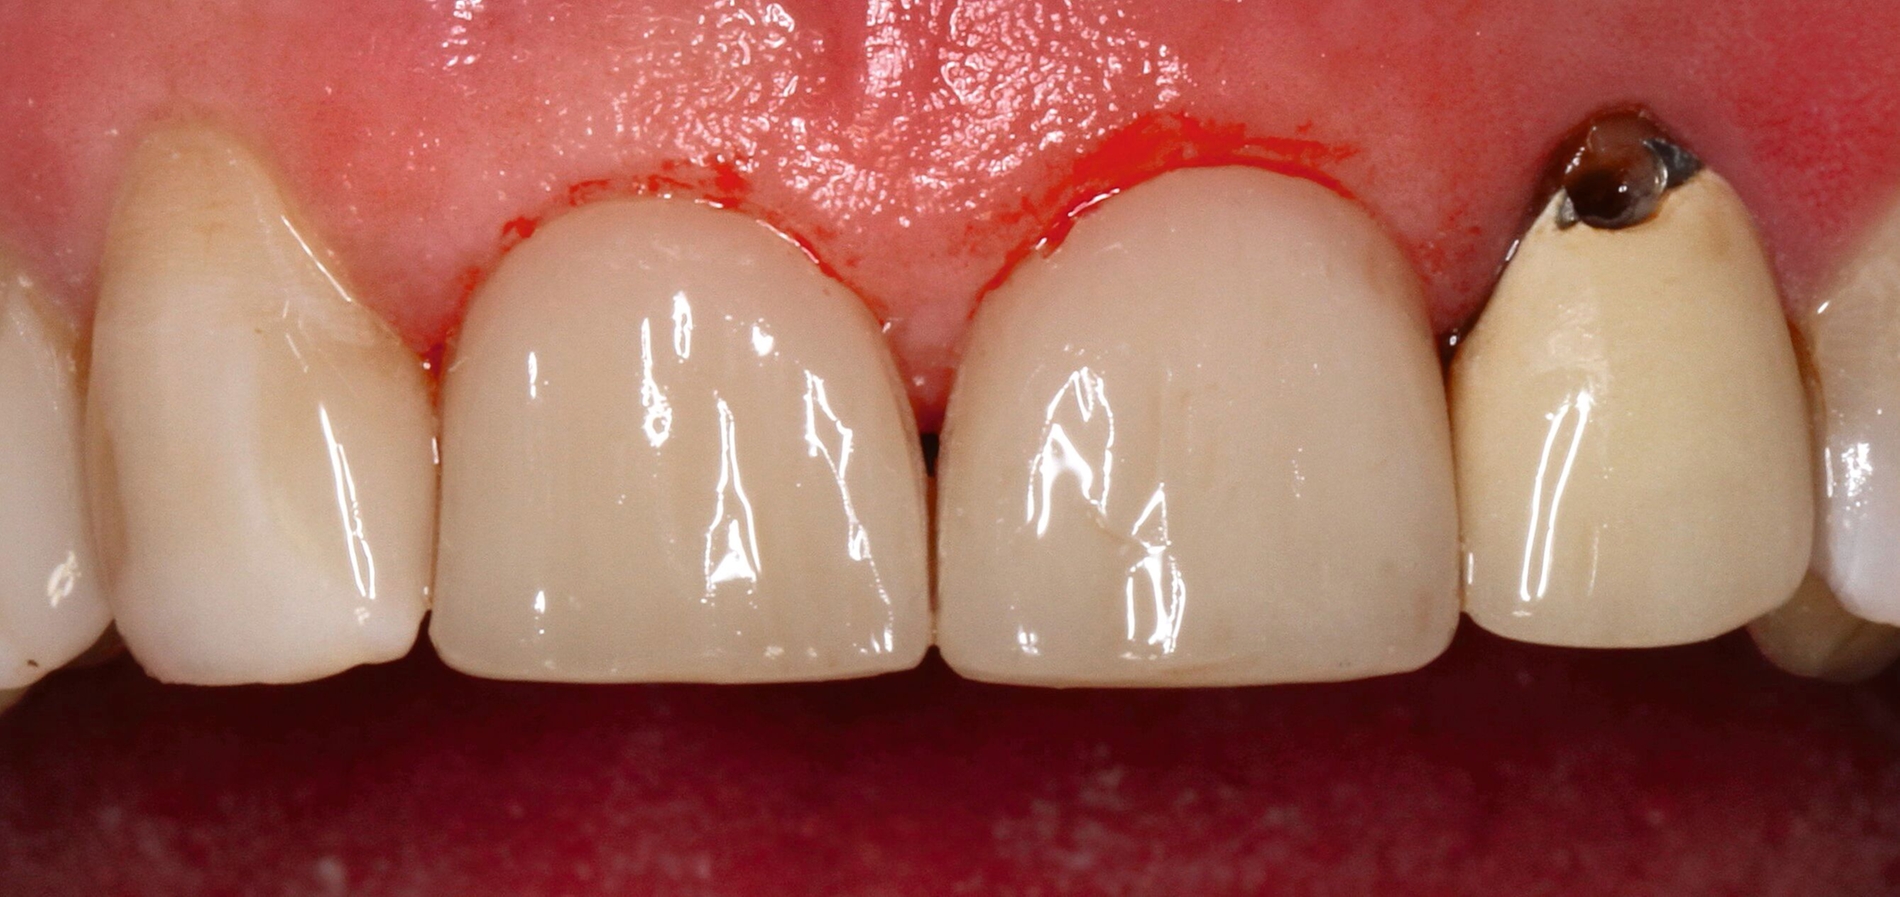

Die dentale Ausgangssituation zeigte im Seitenzahnbereich ein suffizient konservierend und prothetisch versorgtes Gebiss der zweiten Dentition sowie im Frontzahnbereich nicht kariogene Zahnhartsubstanzverluste und eine defekte Krone mit Sekundärkaries (Abbildungen 1 und 2).

Zur Verbesserung der Ästhetik und des Wohlbefindens des Patienten standen die Harmonisierung der Lachlinie und des Frontzahnbogens sowie Farb- und Formkorrekturen der Oberkieferfrontzähne im Fokus. An den Zähnen 11 und 21 waren Zahnhartsubstanzverluste durch Erosion und Attrition zu erkennen. Zahn 23 hatte ebenfalls einen erosiven Defekt, Zahn 13 eine farblich abweichende Kompositrestauration und die Zähne 14 und 24 wiesen keilförmige Defekte zervikal der Kronenränder auf, die einen suffizienten Randschluss haben (Abbildung 1a).

Die Zähne 11, 21 und 32–42 wiesen aufgrund des Zahnverschleißes stark verkürzte klinische Kronen auf. Durch diese Zahnhartsubstanzverluste sind die genannten Zähne über die Zeit elongiert – gut erkennbar an dem in Richtung Okklusionsebene verschobenen Verlauf des Gingivalsaums –, wodurch sich ein frontaler Tiefbiss und in Protrusion eine verzahnte Frontzahnführung im Schlüssel-Schloss-Prinzip mit veränderter Rot-Weiß-Ästhetik adaptiert haben. Daraus resultiert ein verringertes Platzangebot in statischer und in dynamischer Okklusion (Abbildungen 1b und 1d).